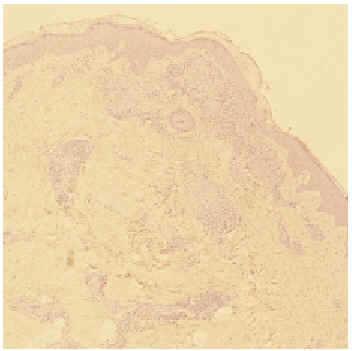

Una mujer de 56 años con antecedentes de histerectomía con doble anexectomía, cirugía de quiste de mama y quemaduras de tercer grado, por explosión de bombona de butano, en extremidades hacía 2 años. Acudió a consulta por presentar, en las cicatrices de estas quemaduras previamente estables, tumefacción con coloración eritematoviolácea y discreta sensación de quemazón al roce, de 2 meses de evolución. En la anamnesis refería sensación de astenia en los últimos meses sin otra sintomatología acompañante. A la exploración las cicatrices correspondientes a las quemaduras mostraban un aspecto hipertrófico e infiltrado, de coloración eritematoviolácea y consistencia firme, en extremidades superiores e inferiores (figs. 1-3). No existía afectación de las cicatrices secundarias a sus intervenciones quirúrgicas ni de la piel sana. El resto de la exploración física general, pulmonar y oftalmológica fue normal. En el estudio histológico de dos muestras cutáneas se observaron en dermis superficial y parte de dermis reticular, varios granulomas de células epitelioides con escasos linfocitos en la periferia y ausencia de caseificación central (figs. 4 y 5).

Fig. 5.--Granulomas de células epitelioides con escasos linfocitos en la periferia y ausencia de caseificación central.